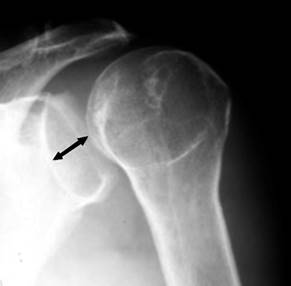

En una luxación glenohumeral anterior, la cabeza humeral se desplaza anterior e inferiormente, lo que da un aspecto de glena vacía en las radiografías AP de hombro; esto no sucede de igual manera en las luxaciones posteriores, donde la cabeza humeral se luxa hacia atrás sin desplazamiento inferior, resultando en la superposición de la cabeza humeral con la glena en la radiografía AP de hombro. La rotación interna del húmero da la apariencia redondeada de la cabeza humeral en la radiografía AP, conocido como “el signo de la bombilla”. Otro signo que ayuda a diagnosticar esta lesión es el “Rim Sign”, que se define como un espacio entre el borde medial de la cabeza humeral y el borde anterior glenoideo > 6 mm en las radiografías AP de hombro (Figura 3).9 En caso de sospecha de una luxación posterior de hombro y en ausencia de los signos previamente mencionados, es necesario tomar proyecciones radiográficas adicionales, como la escápula en Y o proyección axilar (Figura 4); esta última es la mejor para demostrar luxaciones posteriores, aunque puede ser difícil de obtener debido al intenso dolor del paciente.

Figura 3: Proyección anteroposterior de hombro en la cual se evidencia el aumento del espacio entre el borde anterior de la glena y el borde medial de la cabeza humeral (rim sign).